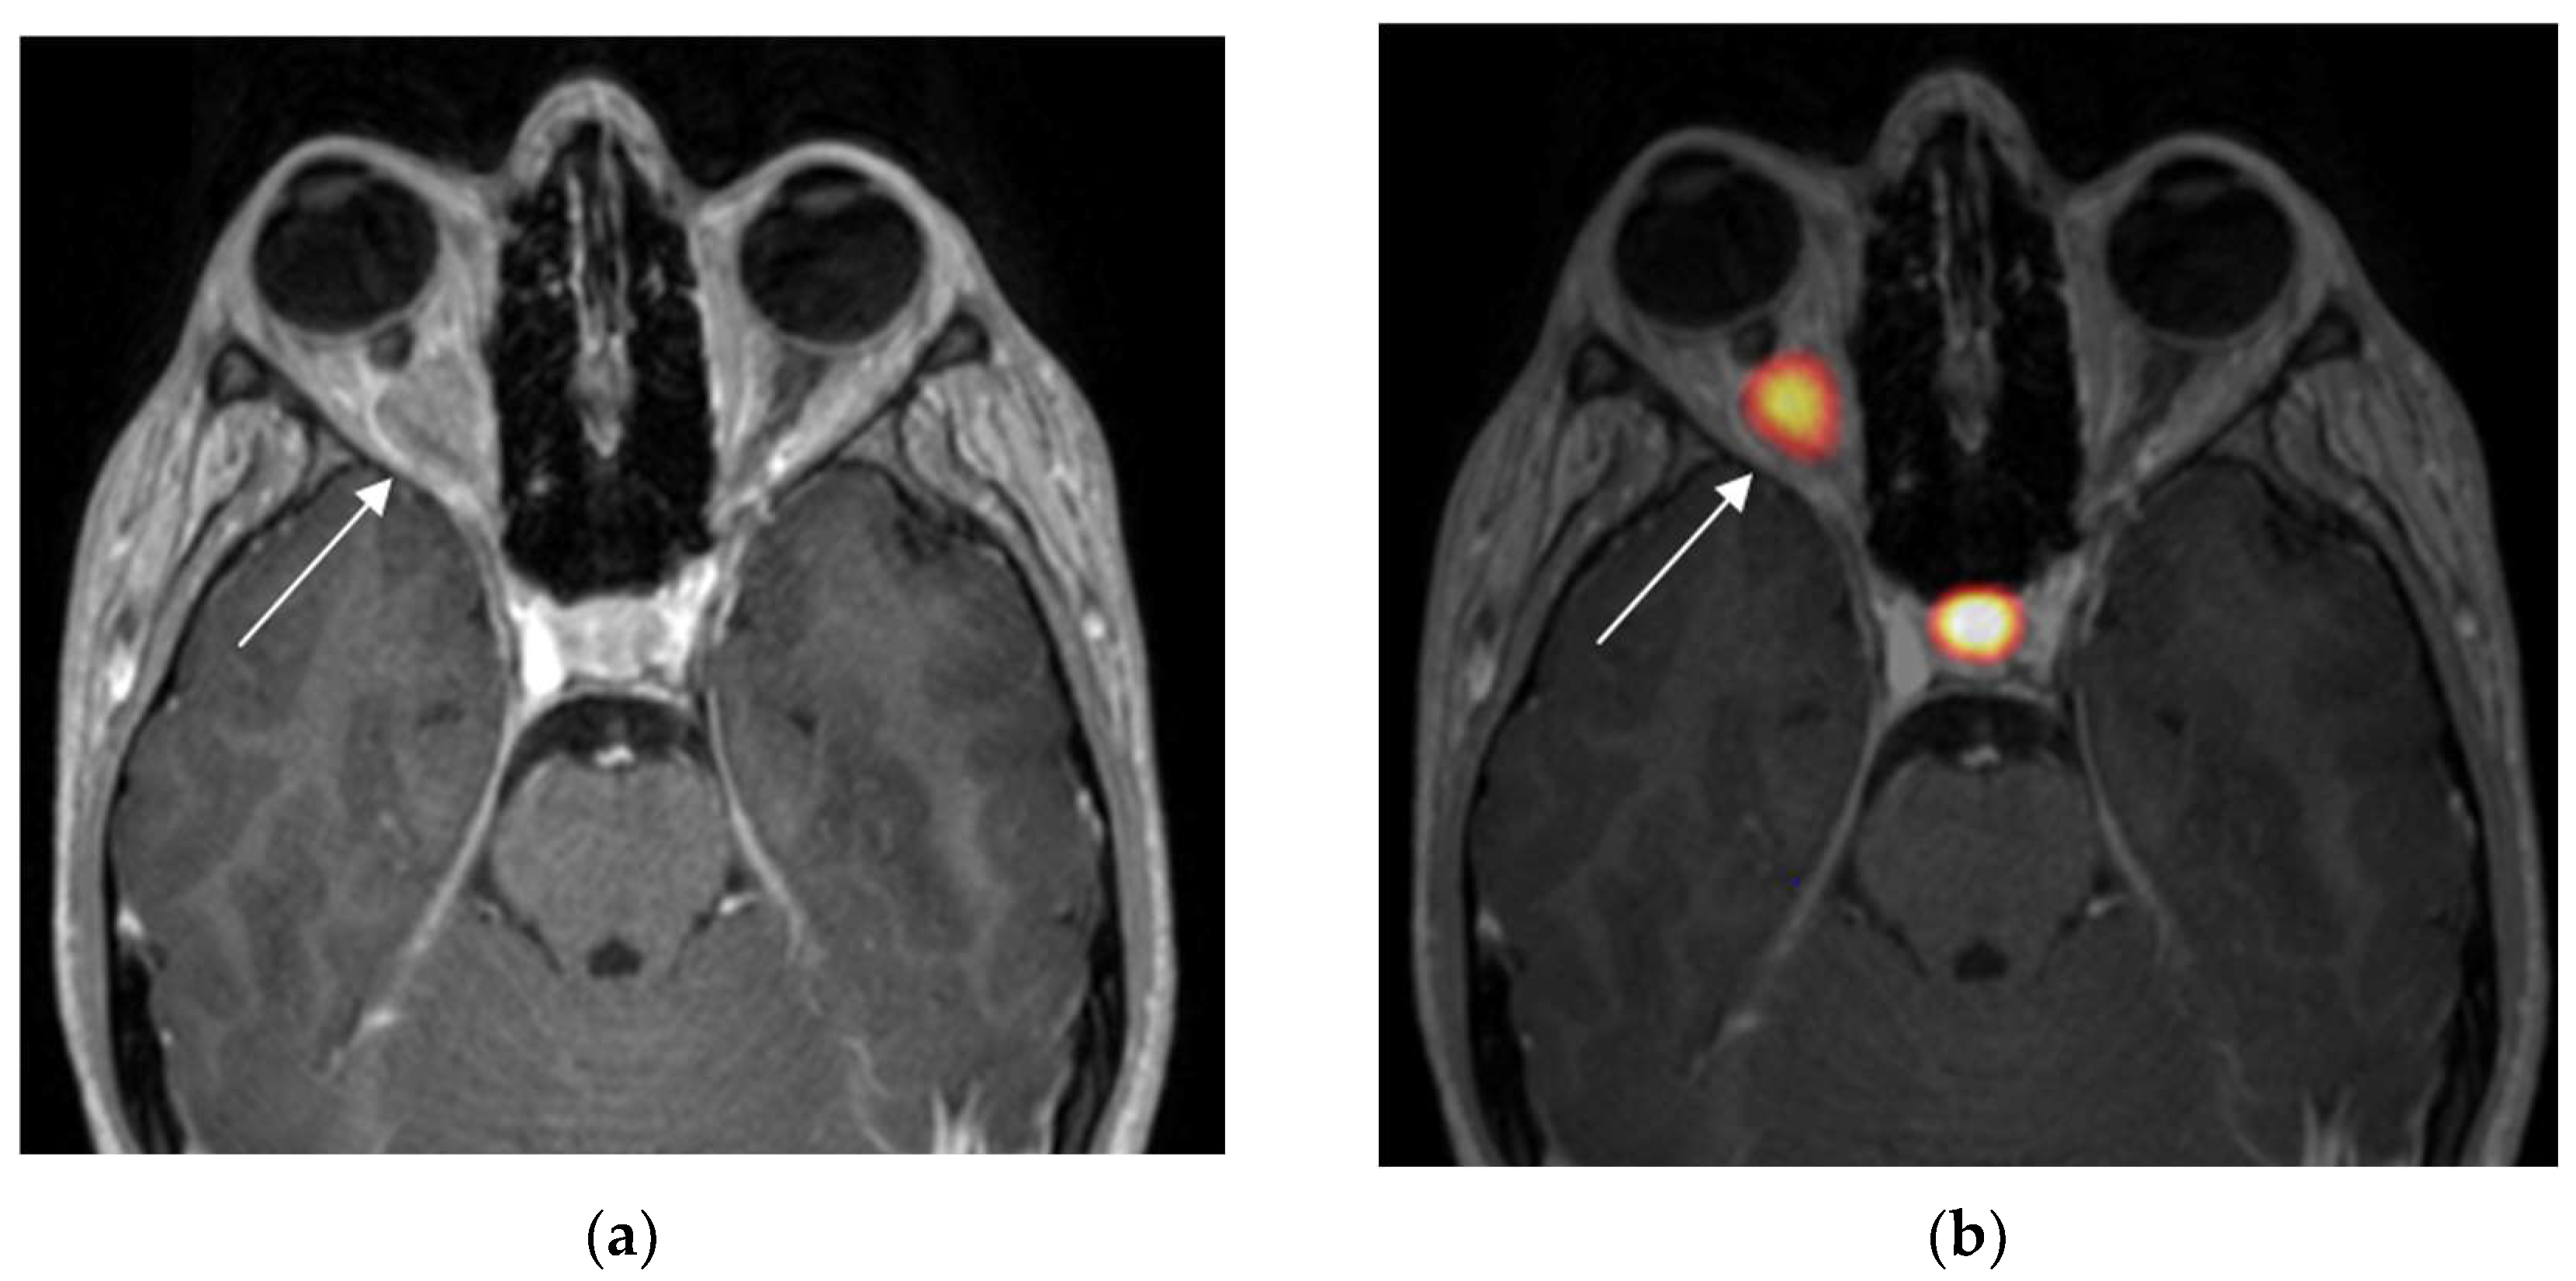

From www.mdpi.com

Diagnostics Free FullText Optic Nerve Sheath Meningiomas Solving Optic Canal Types the optic canal is 4 to 10 mm in length. the optic canal is a round opening located in the posteromedial part of the orbit, within the lesser wing of the sphenoid bone, when viewing the orbit from an anterior perspective. 200 optic nerve canals were assessed and grouped into four types based on the modification of. Optic Canal Types.